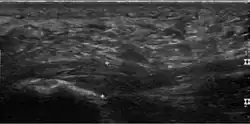

Plantar fasciitis is usually diagnosed by a healthcare provider after consideration of a person's presenting history, risk factors, and clinical examination.[4][17][18] Palpation along the inner aspect of the heel bone on the sole may elicit tenderness during the physical examination.[4][11] The foot may have limited dorsiflexion due to excessive tightness of the calf muscles or the Achilles tendon.[7] Dorsiflexion of the foot may elicit the pain due to stretching of the plantar fascia with this motion.[4][12] Diagnostic imaging studies are not usually needed to diagnose plantar fasciitis.[7] Occasionally, a physician may decide imaging studies (such as X-rays, diagnostic ultrasound, or MRI) are warranted to rule out serious causes of foot pain.

Medical imaging is not routinely needed. It is expensive and does not typically change how plantar fasciitis is managed.[15] When the diagnosis is not clinically apparent, lateral view X-rays of the ankle are the recommended imaging modality to assess for other causes of heel pain, such as stress fractures or bone spur development.[7]

The plantar fascia has three fascicles-the central fascicle being the thickest at 4 mm, the lateral fascicle at 2 mm, and the medial less than a millimeter thick.[19] In theory, plantar fasciitis becomes more likely as the plantar fascia's thickness at the calcaneal insertion increases. A thickness of more than 4.5 mm ultrasound and 4 mm on MRI are useful for diagnosis.[20] Other imaging findings, such as thickening of the plantar aponeurosis, are nonspecific and have limited usefulness in diagnosing plantar fasciitis.[13]